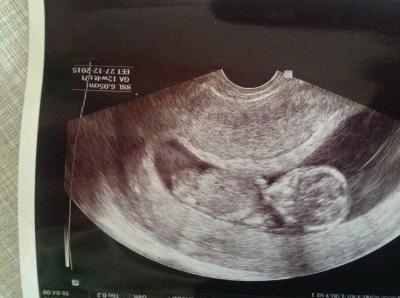

Es ist alles drin, dran und ein wunderschönes Baby. Wurde vom 31.12. auf den 27.12. wieder umdatiert, aber ich möchte trotzdem in dem netten Januarbus bleiben.

Juleika und das Traumbaby mit 6,07 cm